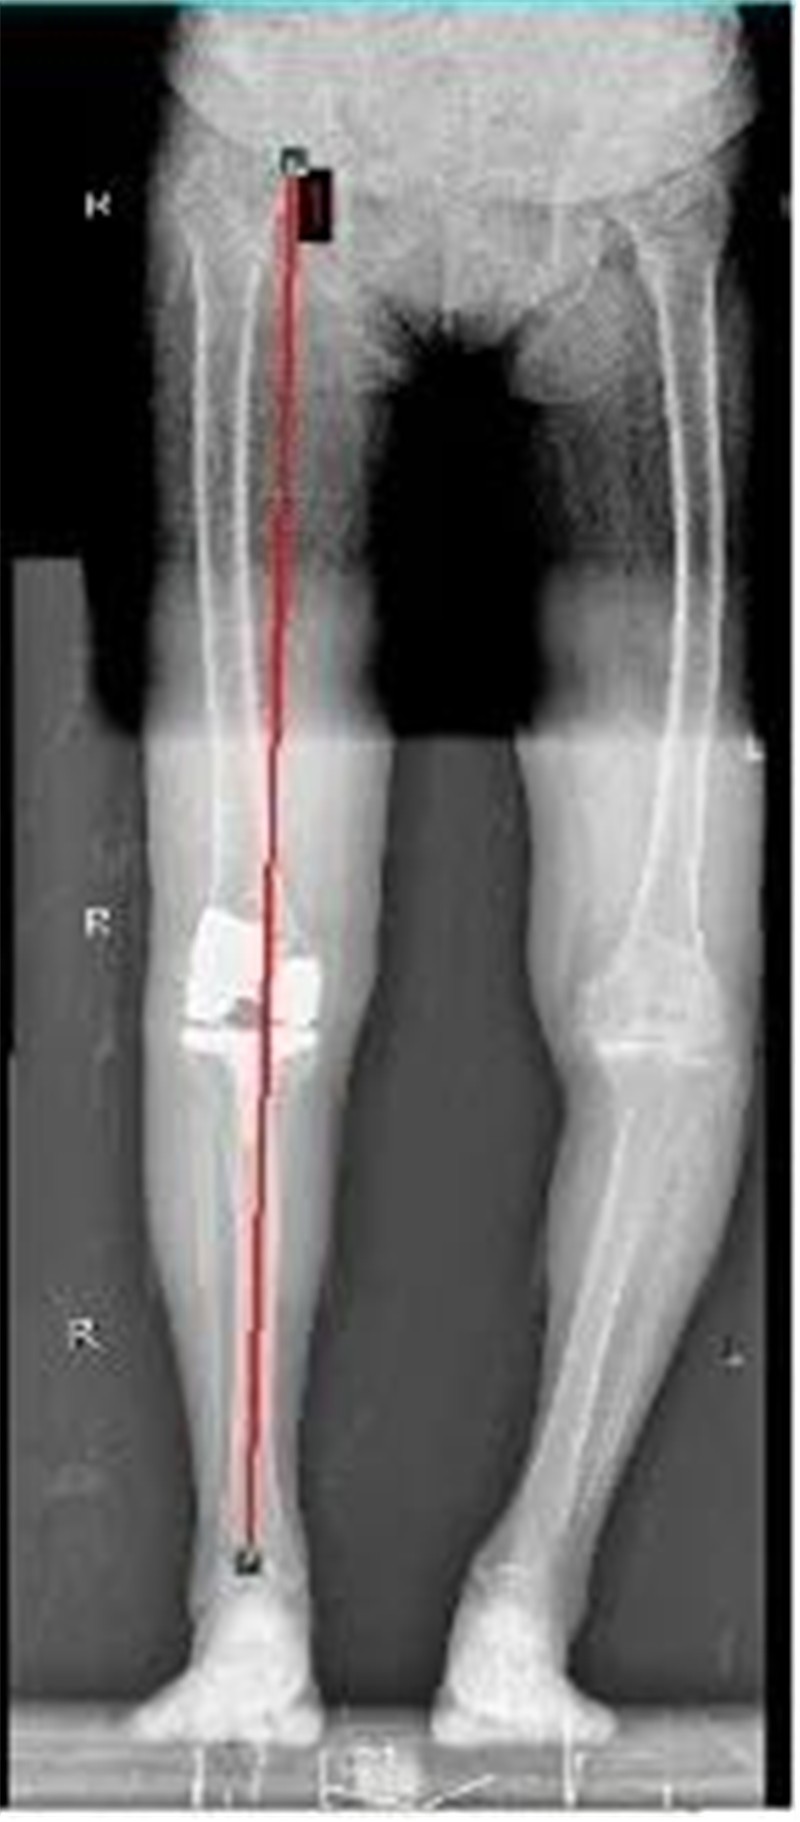

5月7日,我院脊柱关节外科主任潘磊博士为李阿姨进行了“膝关节表面置换术”,通过医学影像可以看到李阿姨右膝关节磨损非常严重,并且出现了严重的外翻畸形(外八字),潘主任医生团队通过进行一个类似“镶牙”一样的手术,把增生老化的关节表面去除后装上合适的人工关节,一个小时左右手术顺利完成。术后医生每天查房指导李阿姨和陈阿姨进行康复练习。

O型腿矫正对比